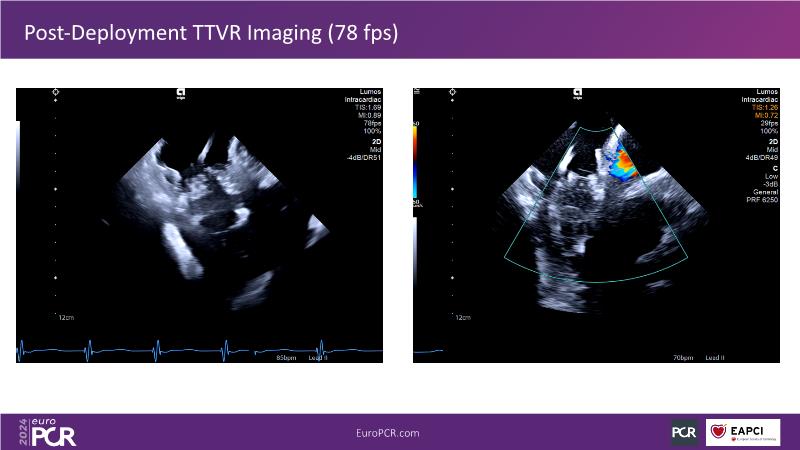

Transformative imaging in the clinical pathway of transcatheter tricuspid valve interventions

Explore this EuroPCR 2024 session for a comprehensive understanding of the imaging pathway in transcatheter tricuspid valve interventions, including diagnosis, therapy, and post-procedural follow-up, discover innovative, transformative imaging techniques such as 4D intracardiac echocardiography and dual-source photon-counting CT, and learn how these innovations can be applied in clinical practice.

- To learn innovative, transformative imaging techniques in transcatheter tricuspid interventions (e.g. 4D intracardiac echocardiography, dual source photon-counting CT)

- To illustrate the potential of these technologies in everyday clinical practice